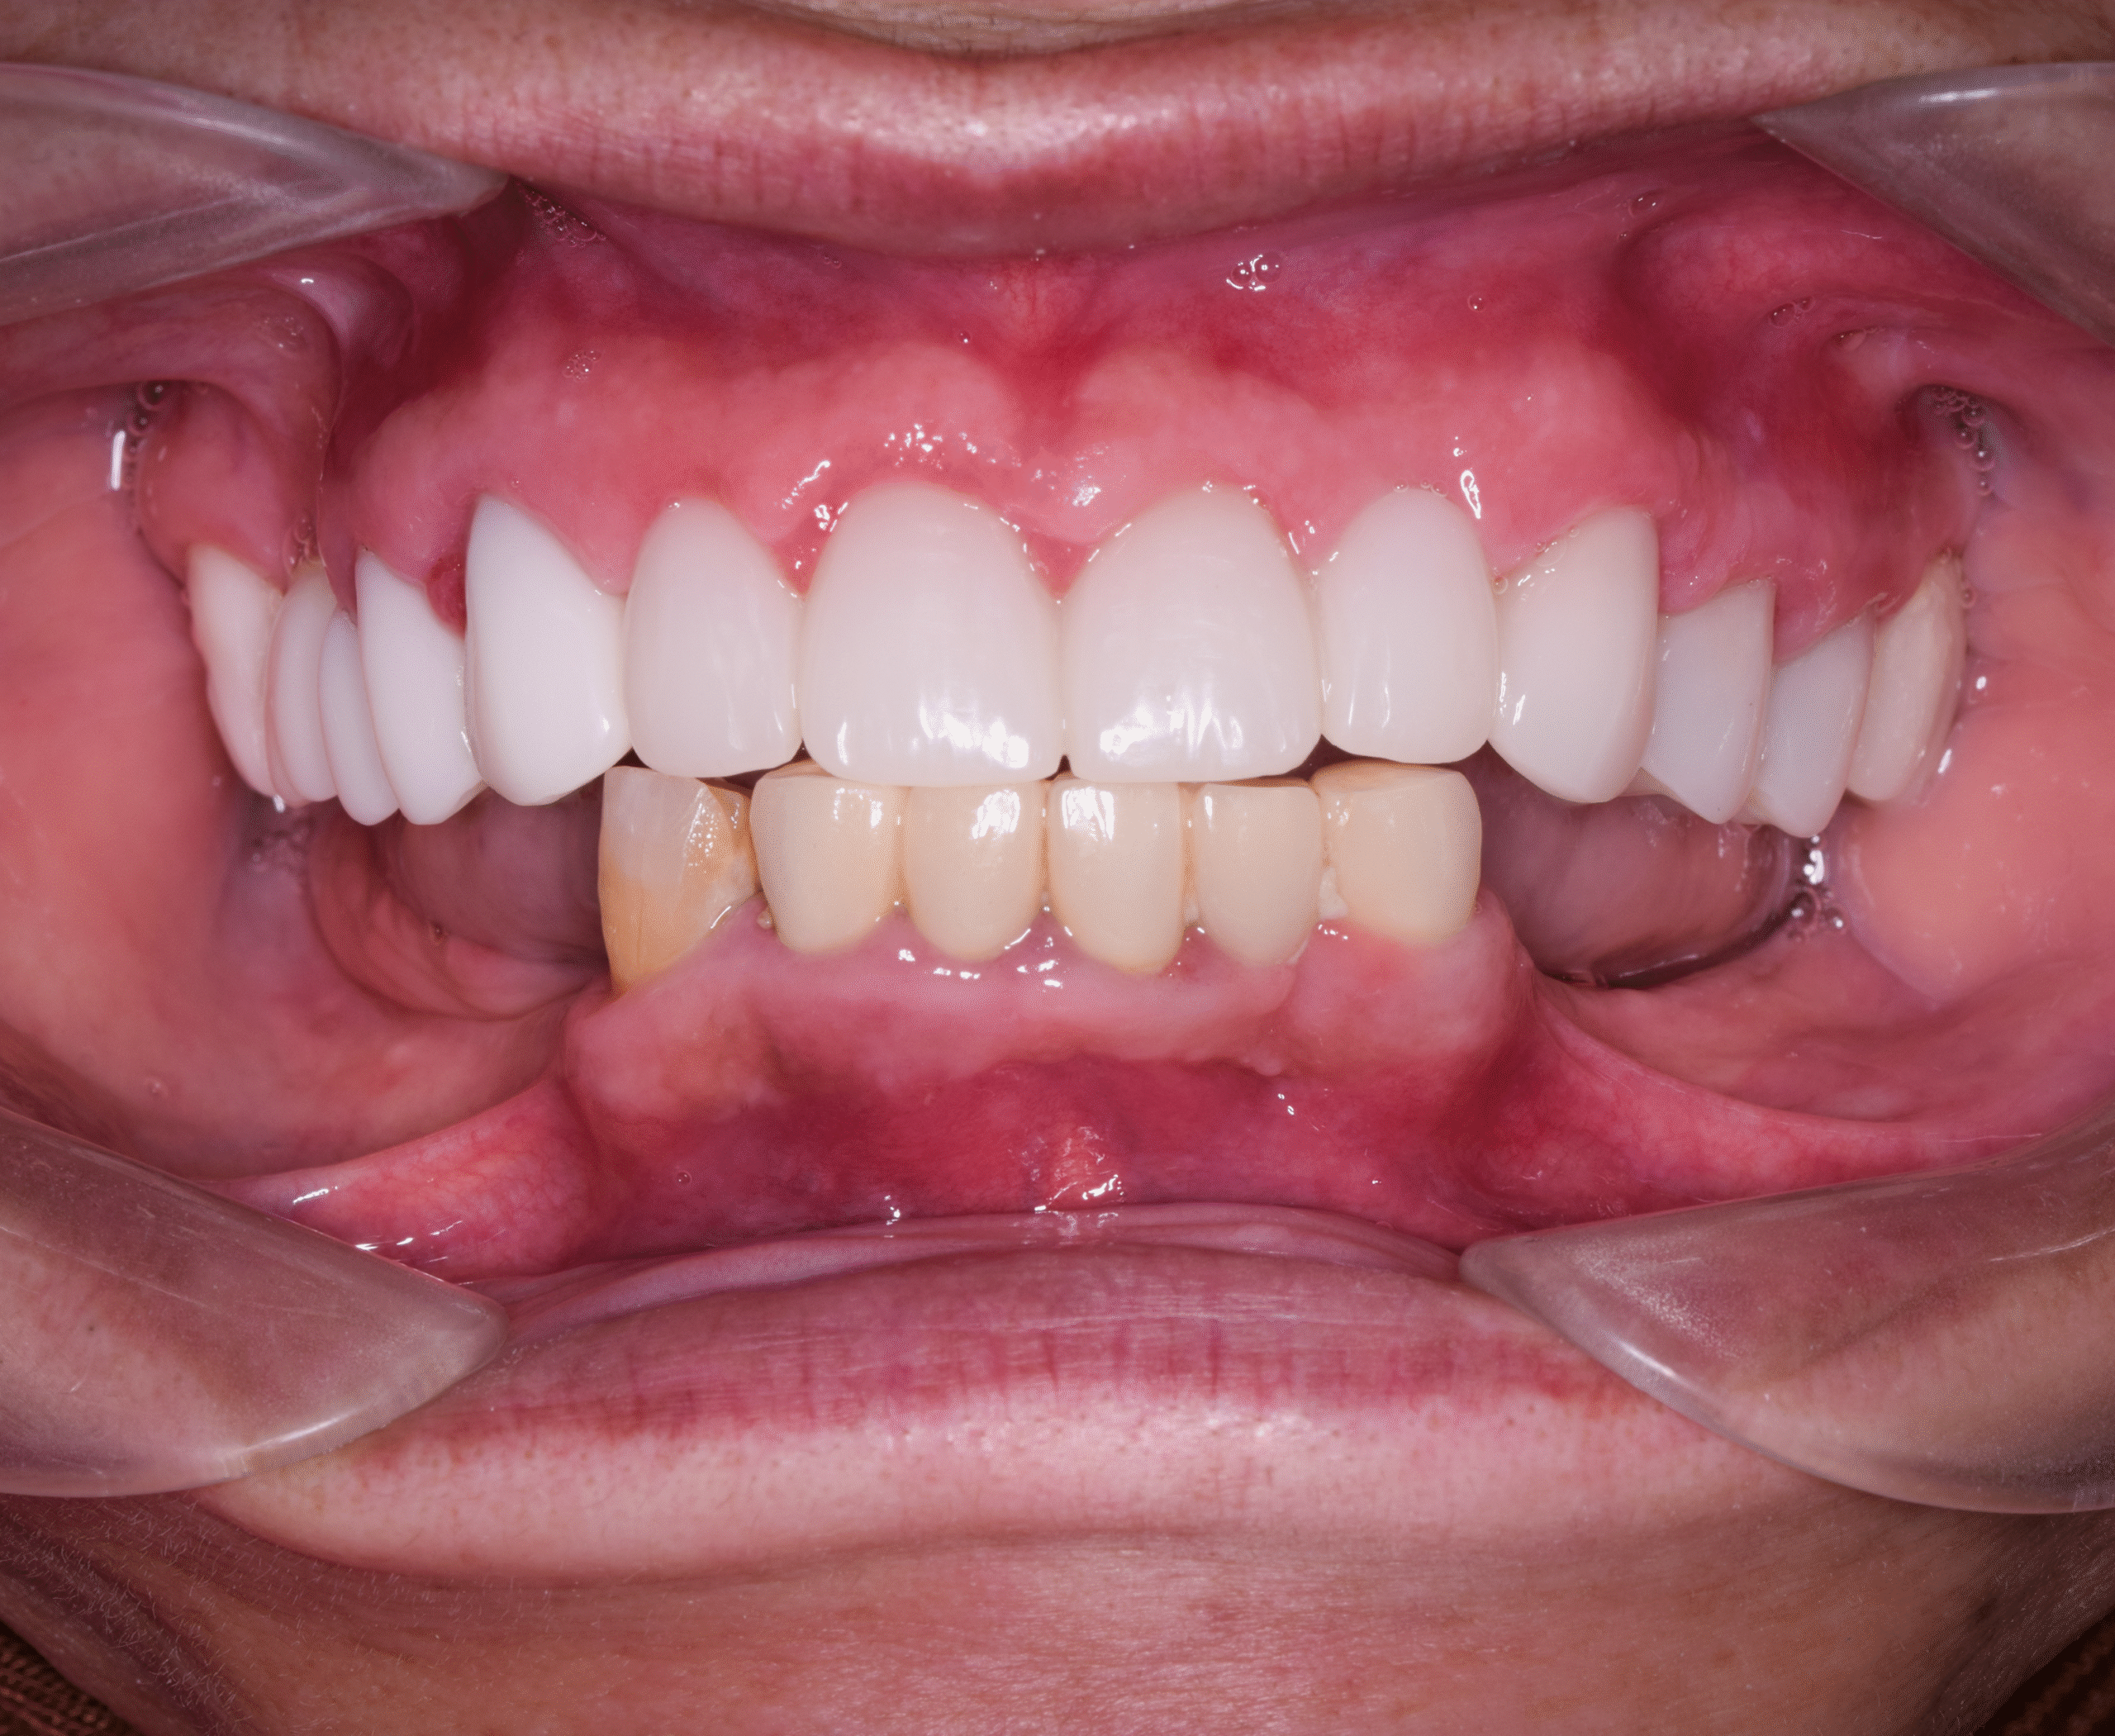

Within five days, Andrew received a fully functional lower-arch implant restoration, while his upper teeth were preserved and renewed with advanced restorative care.

The combined approach gave him:

- Natural-looking upper teeth

- A stable and fully functional lower jaw

- Restored confidence

- A long-term solution with predictable outcomes